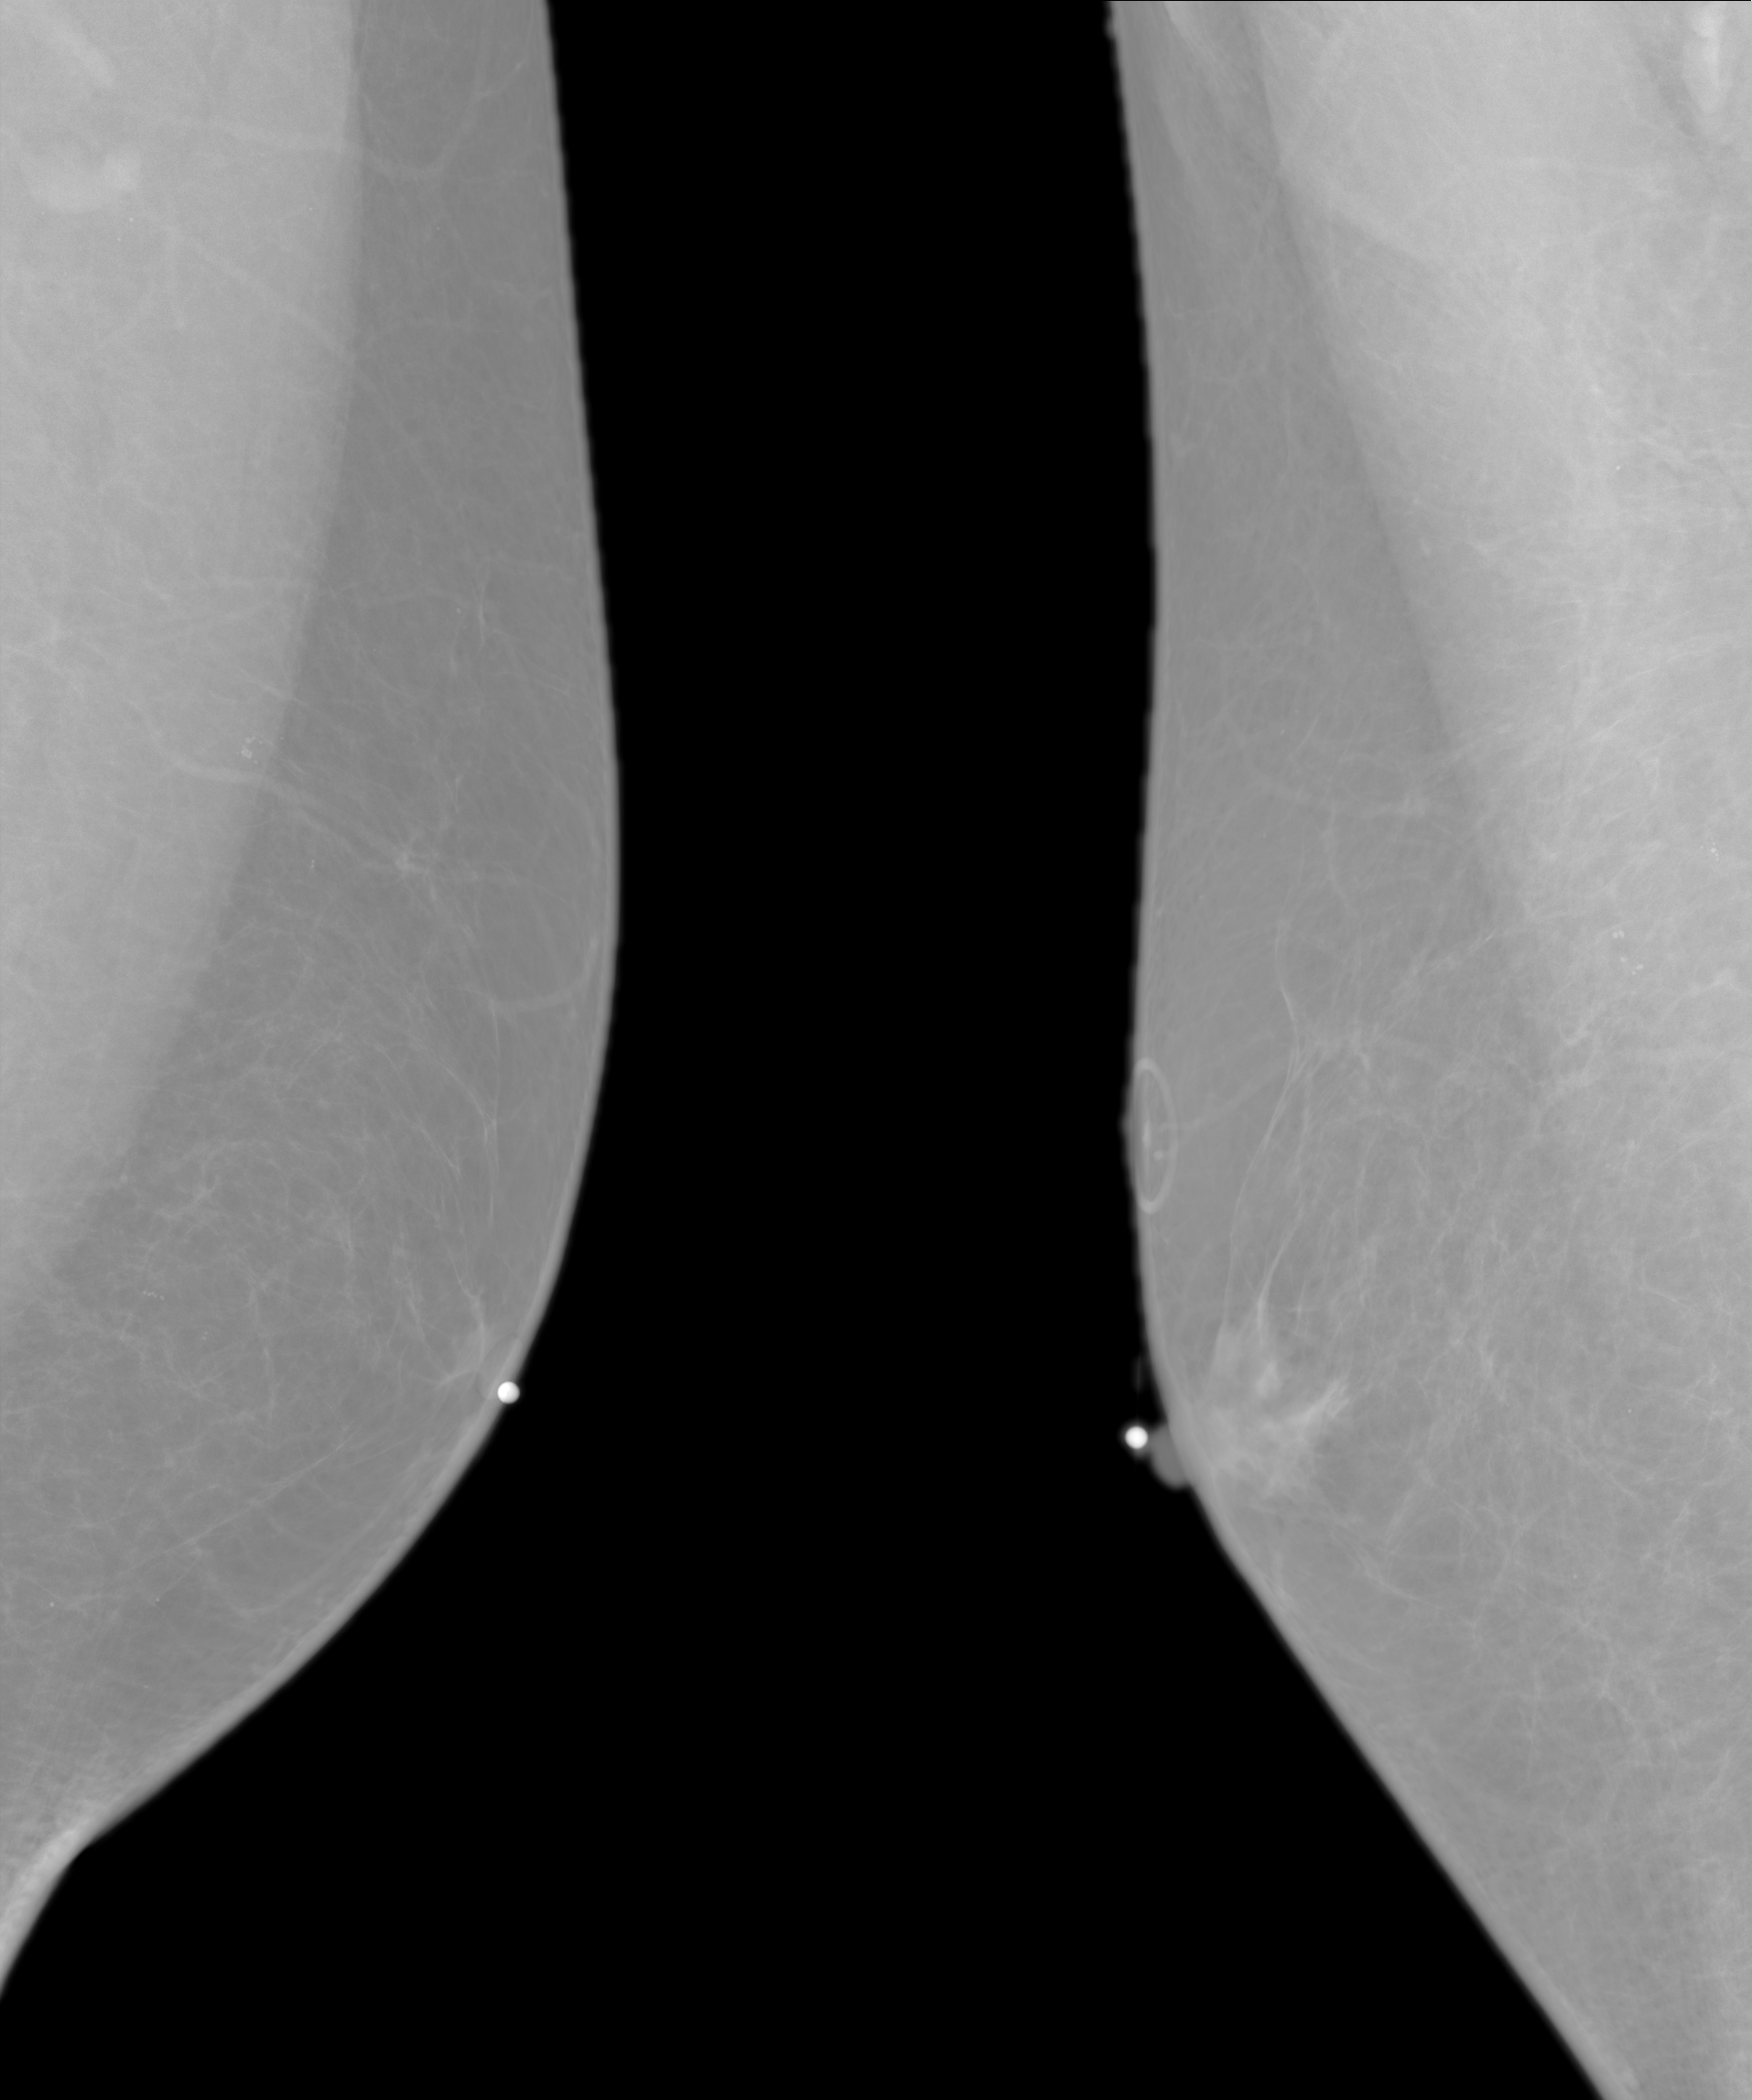

A few weeks ago I reported to my doctor that I had a pressure-sensitive lump in my right breast. This happened the very next day:

It’s a composite of two mammogram images, of my left and right breasts, respectively, with the small white dots marking the obvious targets and the ring above the right dot surrounding a mole. You will be unsurprised to know that the radio-opaque markers came on cheery flowered stickers:

Given such small numbers, what you see up there on the right is almost certainly an unusually tender and mostly unilateral case of gynecomastia, which was the diagnosis relayed from the radiologist after the imaging. Because things are different for guys, there’s an appointment with an oncologist (yes, she specializes in breast cancer) and, perhaps, some biopsy samples in my immediate future.

They triage the appointment schedule based on radiographic evidence. Fortunately, I’m not on the hot list.